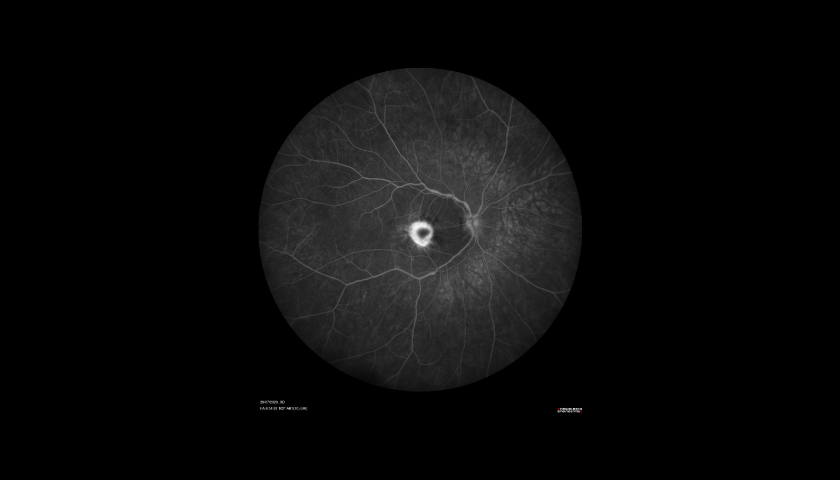

A Angiografia Fluoresceínica (AF) é um exame auxiliar de diagnóstico e monitorização em oftalmologia que permite visualizar e analisar a circulação da retina, com o objetivo de identificar possíveis alterações ou lesões que expliquem um determinado quadro clínico.

A Angiografia é indicada principalmente em patologias como a Retinopatia Diabética (RD), a Degenerescência da Idade (DMI), as oclusões vasculares (tromboses) e os tumores oculares. Utilizando o Spectralis® HRA+OCT (com as lentes de 30o, 55o ou 102o), é um procedimento de diagnóstico no qual uma sequência rápida de fotografias é tirada após injeção de um corante para documentar a circulação sanguínea da Retina e também da Coróide e assim ajudar a diagnosticar e tratar muitas doenças oculares.